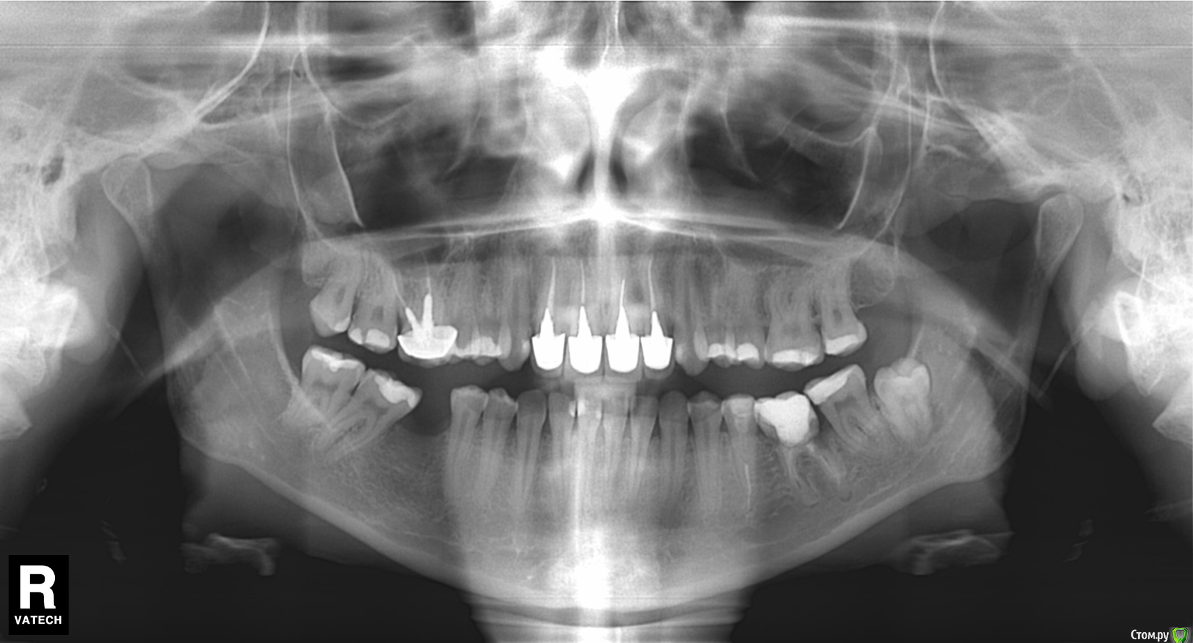

MariaF Опубликовано 10 февраля, 2016 Поделиться Опубликовано 10 февраля, 2016 (изменено) Добрый день, В 2002 году на передние зубы были установлены 4 металло-керамические коронки (cнимок прикрепила).На потемнение десны я не обратила внимания, поэтому когда именно это произошло сказать не могу, но думаю давно. Сейчас собралась их менять и вдруг задалась вопросом о деснах.Важно уточнить, что менять коронки приходится в Турции, и не смотря на мой неплохой турецкий многих терминов я не знаю. Насколько я поняла, под десной во всех 4-х зубах осталась часть родного зуба. Врач сначала удалил инструментом две самые передние коронки ( на их место поставил светлые штифты, материал похож на керамику).Двойки зубы врач предпочел не вытаскивать полностью, а спилить (т.к. побоялся сломать родную часть зуба).В результате остались небольшие части металла. Немного подрезал десну, скорее в косметических целях, т.к. 1 зуб был вроде как короче (фото прикрепила).Теперь ждем заживления.Врачом был выявлен переодонтит, неужели лечение состоит только в "самоизлечении", т.к. ничего назначено не было. Поставил временные коронки (фото прикрепила, как раз на нем хорошо виден большой потемневший участок десен) Новые коронки будут E-max. Хотела бы узнать, от чего могло произойти потемнение, причем такое обширное: из-за 'мертвых' зубов или из-за металла?Если из-за метала, то не будет ли логичнее его удалить? Спасибо за советы! Изменено 10 февраля, 2016 пользователем MariaF 1 1 Ссылка на комментарий

MariaF Опубликовано 17 февраля, 2016 Автор Поделиться Опубликовано 17 февраля, 2016 Уважаемые доктора, Попросила администратора вновь открыть тему.Может у вас будут какие-то предположения на эту тему. Новые коронки все еще не были установлены. Насколько я поняла в состав старых входило серебро, которое и могло дать потемнение. Но потемнение произошло не только у самого зуба, но и выше, что видно на фото. Ссылка на комментарий